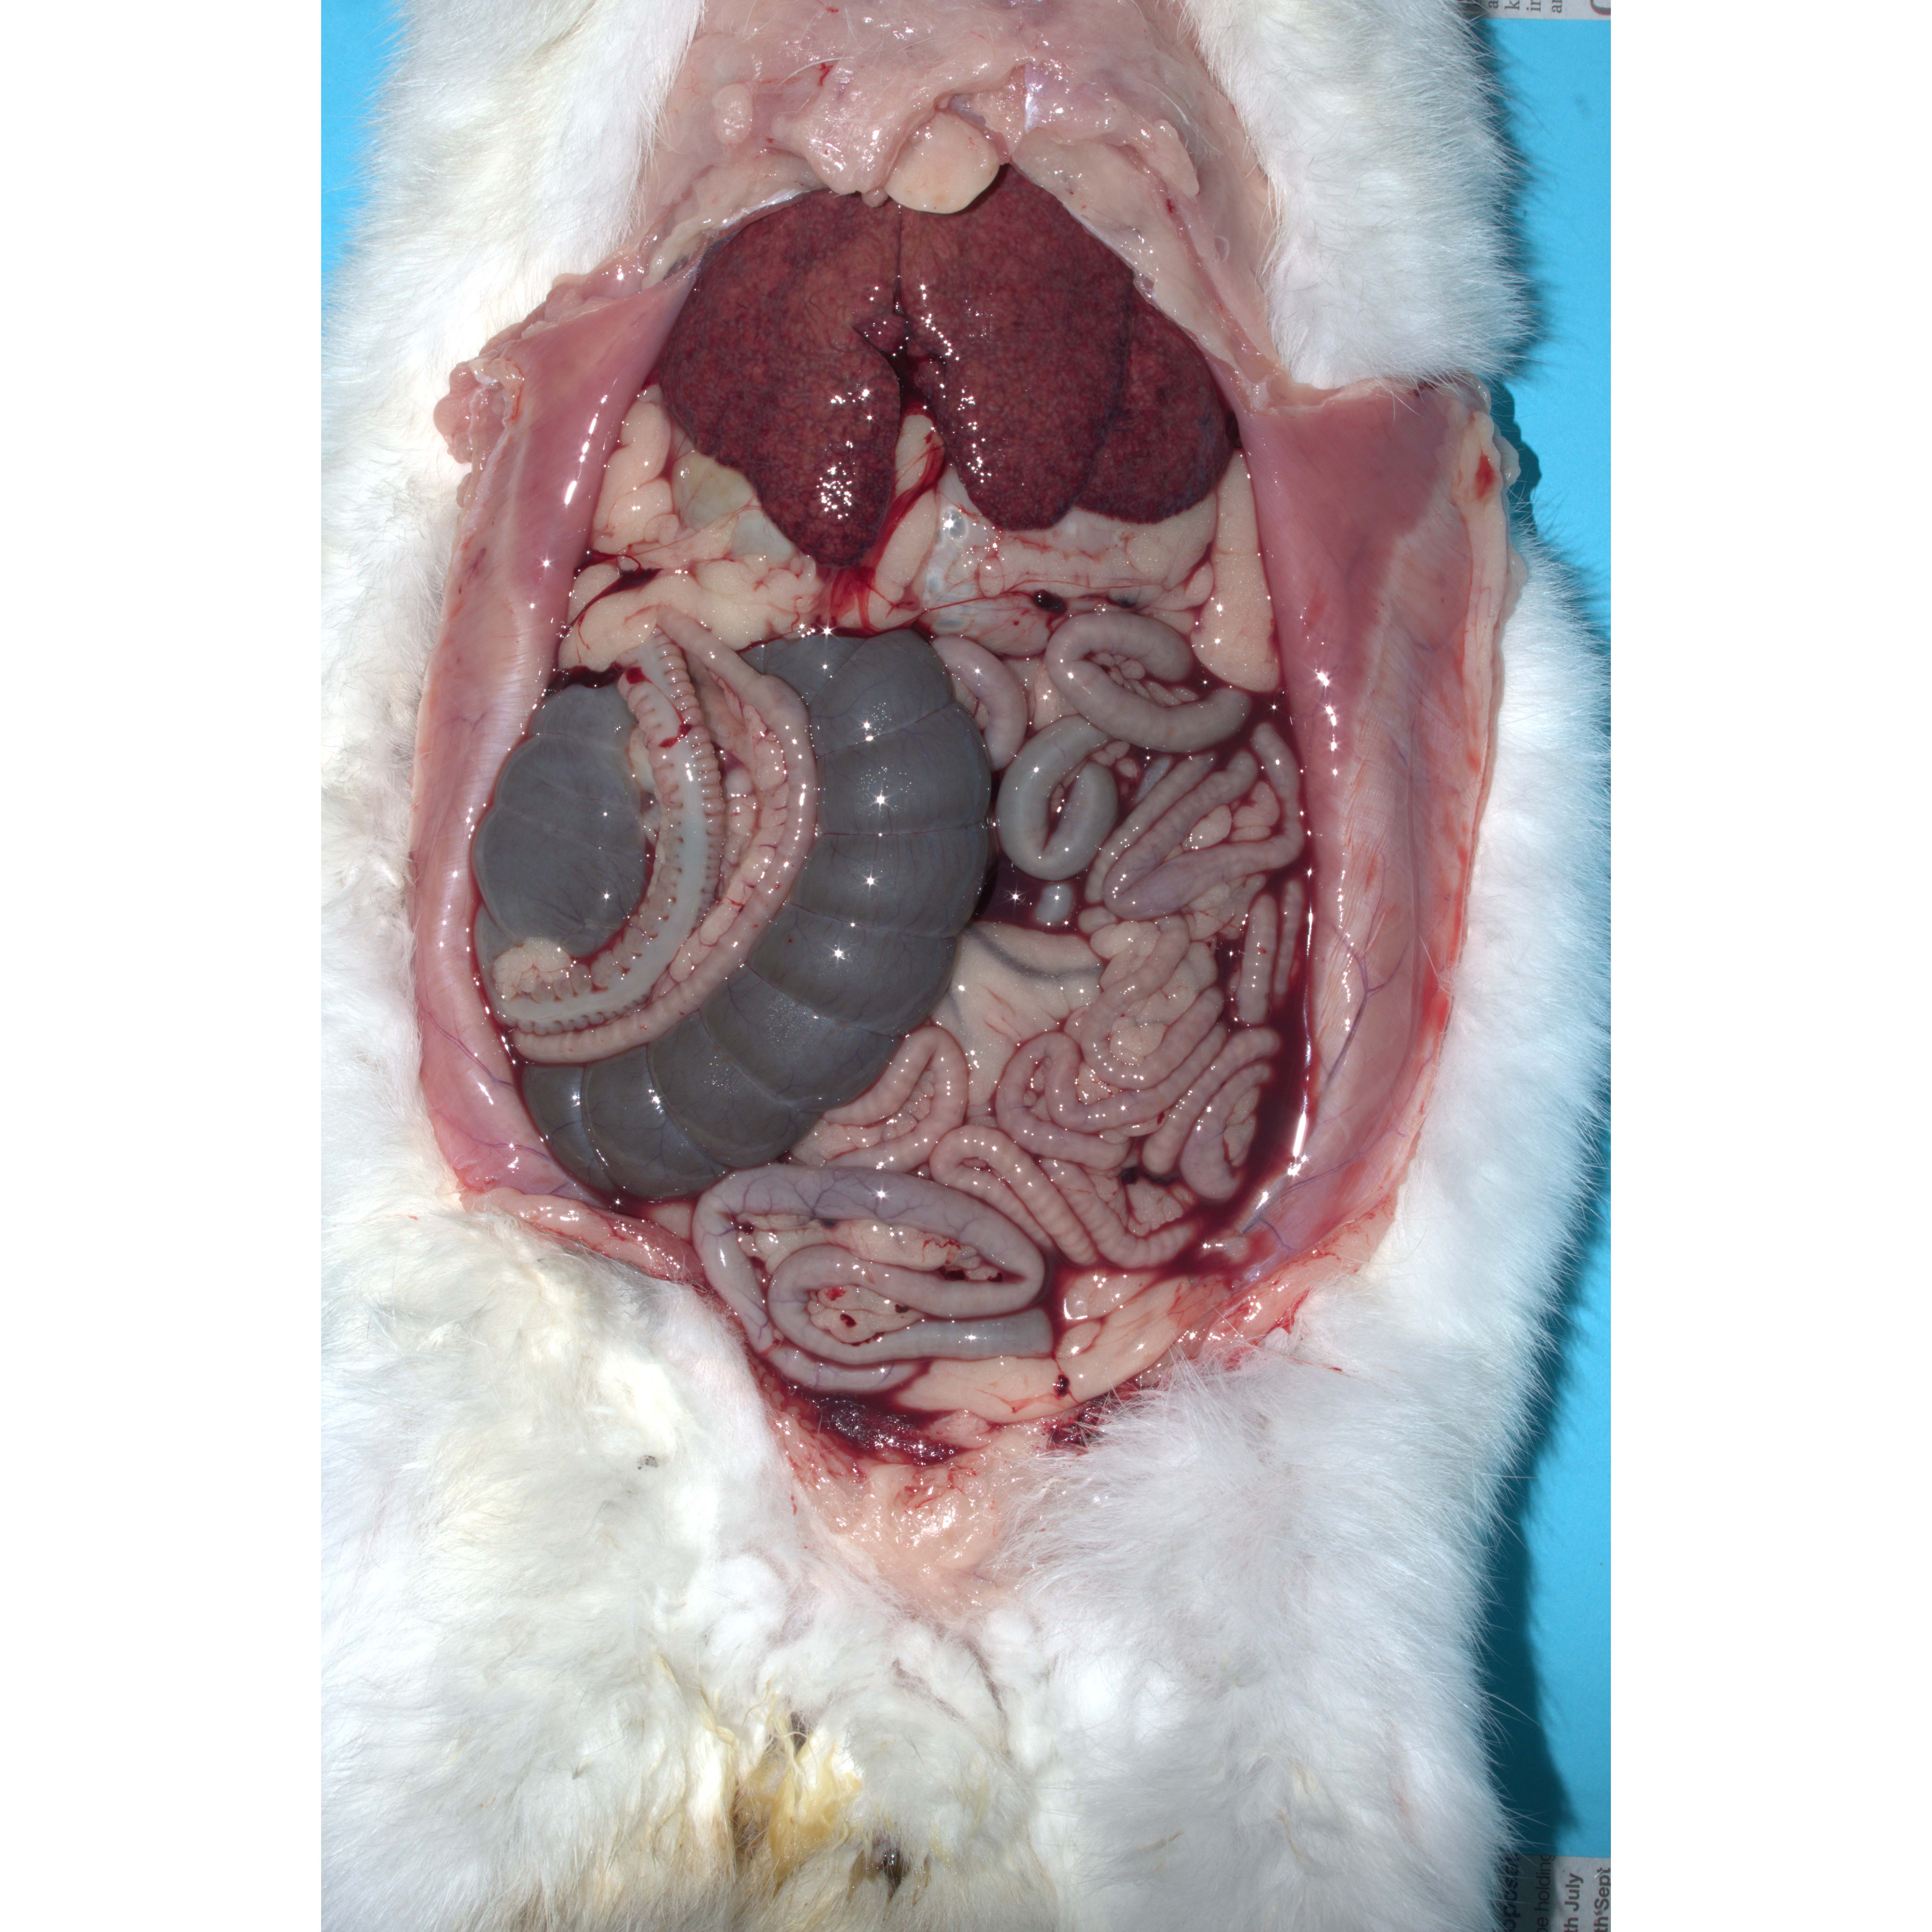

This picture shows the abdominal contents of an adult lionhead neutered male rabbit that died the day after a general anaesthetic for dentistry. The liver is swollen and pale and there is haemorrhagic fluid in the abdomen. Histopathology showed characteristic signs of RHD, including hepatocellular necrosis. PCR testing confirmed the presence of RHDV2.